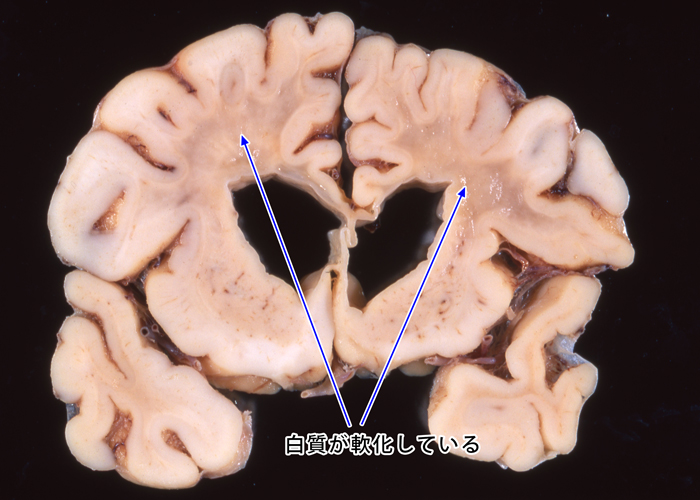

進行性多巣性白質脳症

脱髄疾患・髄鞘破壊性疾患

Demyelinated disease